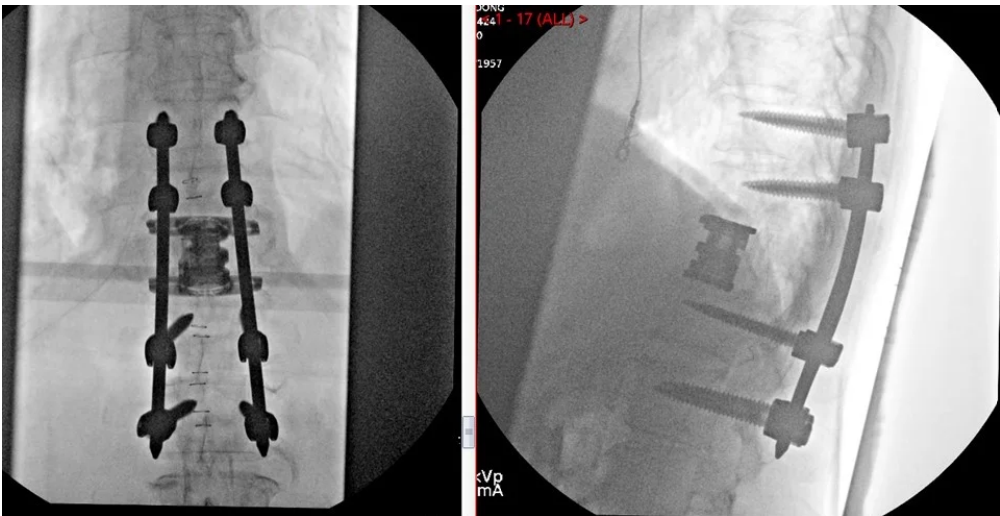

Posterior Lumbar Spine Surgery

Lumbar Fusion

Deformity Correction